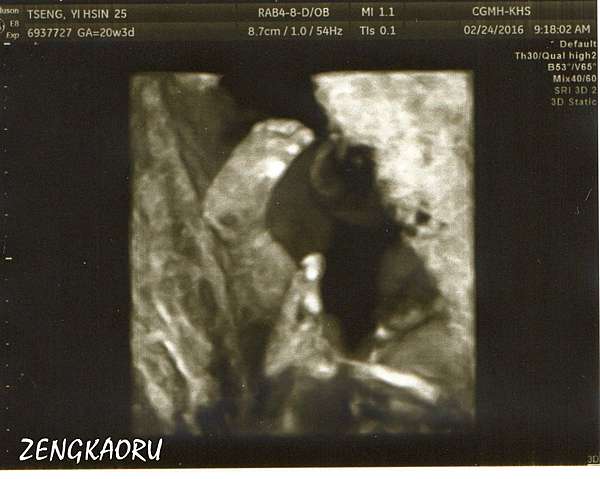

懷孕21週 高層次超音波 4d超音波看到寶寶真面目 性別正式揭曉 小環妞幸福足跡

我們的新成員日記 產檢 2d 3d 4d 高層次超音波 心臟超音波 鳥先生 鳥夫人

白帥帥20週 高層次超音波經驗 派大馨的走跳人蔘 痞客邦

博愛蕙馨醫院 4d影像中心